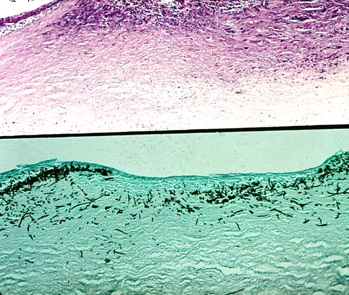

诊断:角膜溃疡(霉菌)

注释:组织切片显示溃疡形成,深层炎症反应。真菌染色显示菌丝深入基质层。